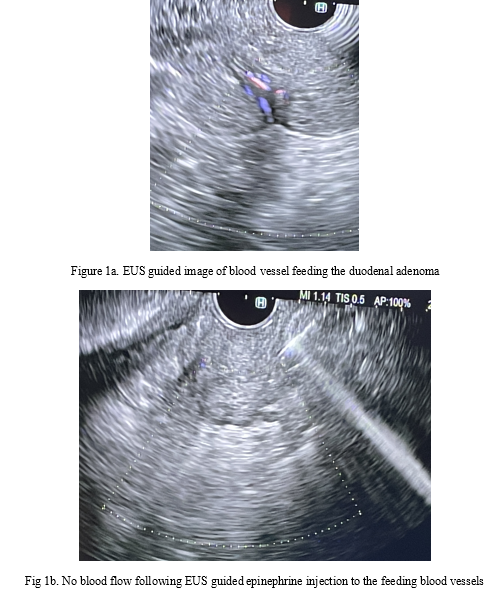

Endoscopic ultrasound was performed to make sure the lesion is not invasive malignant lesion,  prior to EMR. A linear array echoendoscope (Olympus America) was passed into the esophagus and advanced into the stomach, and ultrasound imaging of the liver and retroperitoneum appeared fine. The duodenum revealed the large duodenal lesion was indeed mucosal in origin and no evidence of infiltrative malignancy noted. The muscularis propria was intact and no lymph adenopathy noted. The large feeding arterial blood vessel was noted using doppler and 3 mL of 1 in 10,000 epinephrine was injected which resulted in vasoconstriction and doppler showing no blood flow (Figure 1). EMR was performed using gastroscope (Olympus America).

Figure 1a. EUS guided image of blood vessel feeding the duodenal adenoma

Fig 1b. No blood flow following EUS guided epinephrine injection to the feeding blood vessels